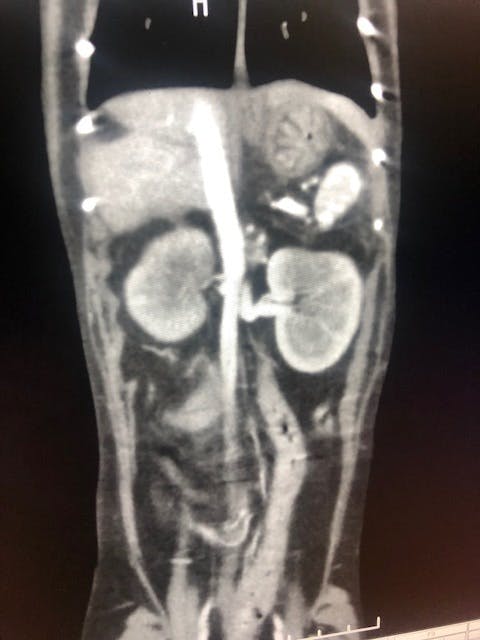

その日のうちに超音波検査、翌日CT検査を実施し膀胱に近い腸に腫瘍があるという事でした。

院長先生曰く、腎臓周りも見え方がおかしいのと腸管の腫瘍からリンパ腫が疑わしいという事で、腸管の腫瘍の切除と腎臓の検査が必要と言われました。

CT検査で院長先生がここが悪いと見せてくれた画像(素人目にはあまりわからなかったです。。)